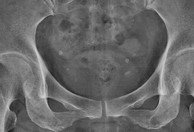

Phleboliths "vein stones"

• Represent calcification within venous structures

• Particularly common in the pelvis where they may mimic ureteric calculi

• Focal calcifications, often with radiolucent centers (another helpful sign if present to distinguish them from ureteric calculi).

• This appearance is attributed to calcification peripherally within the vessel, and is frequently seen on abdominal radiographs.